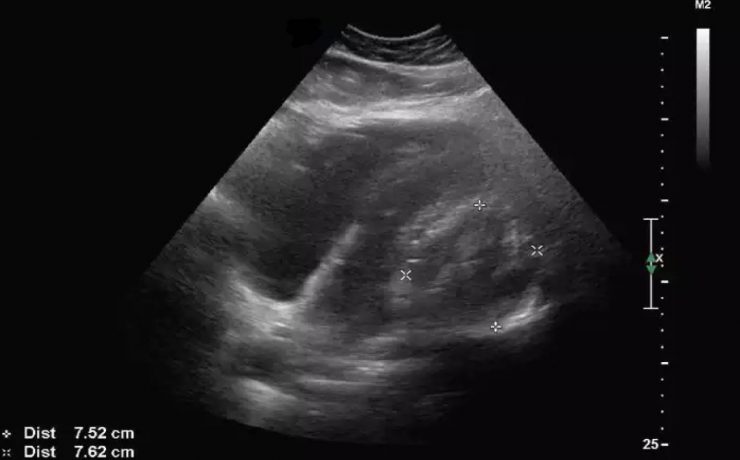

Alteraciones segundo trimestre de gestación.

Objetivo determinar la asociación entre ausencia e hipoplasia del hueso nasal fetal y alteraciones estructurales y/ o cromosómicas en el neonato, en la población en general en el ultrasonido del segundo trimestre. La gran mayoría de malformaciones congénitas no son prevenibles ya que constituyen accidentes en la organogénesis embrionaria y